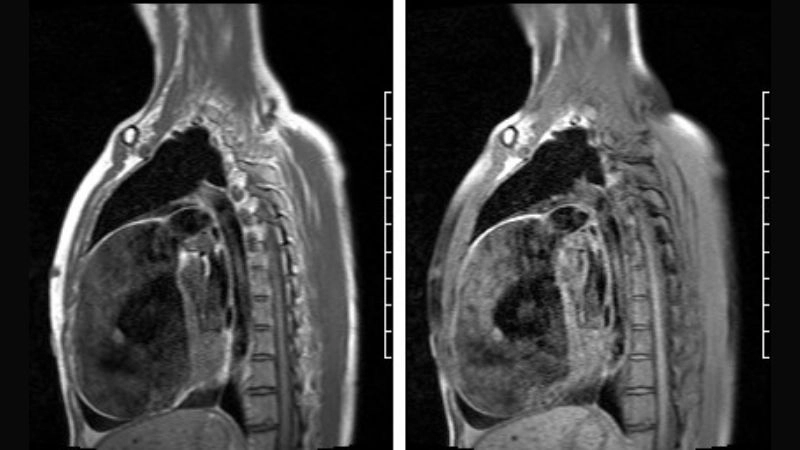

Images visual examples of Uhl's anomaly

Uhl’s anomaly is a rare congenital heart condition characterized by the near-complete absence of the right ventricular myocardium, resulting in a thin-walled and weakened heart chamber.